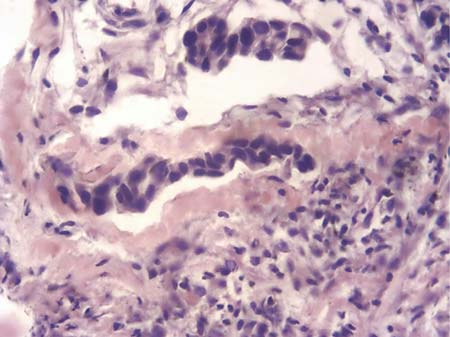

В результате изготовления серийных срезов с реакцией МКАТ против пан-цитокератинов был выявлен 551 непоражённый ЛУ, 38 — с наличием изолированных клеток опухоли или их кластеров (рис. 1), 122 — с микрометастазами (рис. 2), 479 — с метастазами различного объёма и 73 ЛУ, полностью замещённых опухолевой тканью. В двух последних случаях метастазы хорошо определялись и без иммуногистохимического исследования. Сеть кровеносного микроциркуляторного русла ЛУ выявлялась по экспрессии МКАТ против CD31 в эндотелии и против коллагена IV типа в базальных мембранах сосудов (рис. 3).

Рис. 3. Экспрессия CD31 в эндотелии кровеносных сосудов. LSAB-метод с докраской гематоксилином. ×400